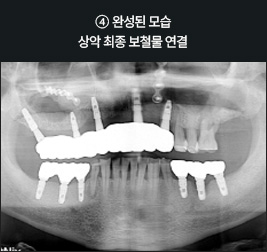

올온식스 풀아치 임플란트 사례      I

치료 기간 : 2021.05.08 ~ 2021.11.19

I      올온식스 풀아치 임플란트 사례      I